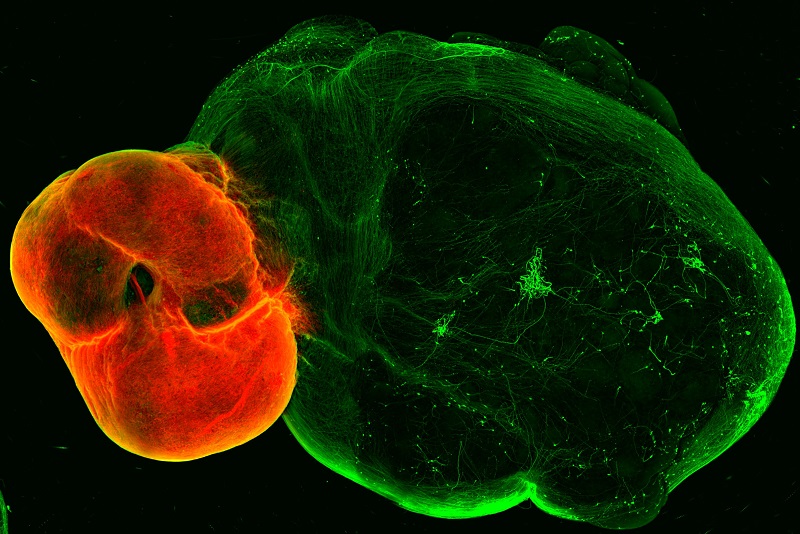

中脑腹侧(红色)中的多巴胺能神经元投射到纹状体和皮质组织(绿色)。图片来源:丹尼尔·鲁曼/奥地利科学院分子生物科技研究所

该团队首先开发了所谓的中脑腹侧、纹状体和皮质的类器官模型,这是多巴胺系统中神经元连接的区域。然后,他们开发了一种将这些类器官融合在一起的方法。就像在人脑中发生的那样,中脑类器官的多巴胺能神经元向纹状体和皮质类器官发出投射。

研究人员观察到了高水平的多巴胺能神经支配,以及多巴胺能神经元和纹状体、皮质神经元之间形成的突触。当他们刺激含有多巴胺能神经元的中脑时,纹状体和皮质中的神经元对刺激有反应。论文第一作者丹尼尔·鲁曼表示,他们成功地在体外模拟了多巴胺能回路,因为细胞不仅连接正确,而且还能共同发挥作用。